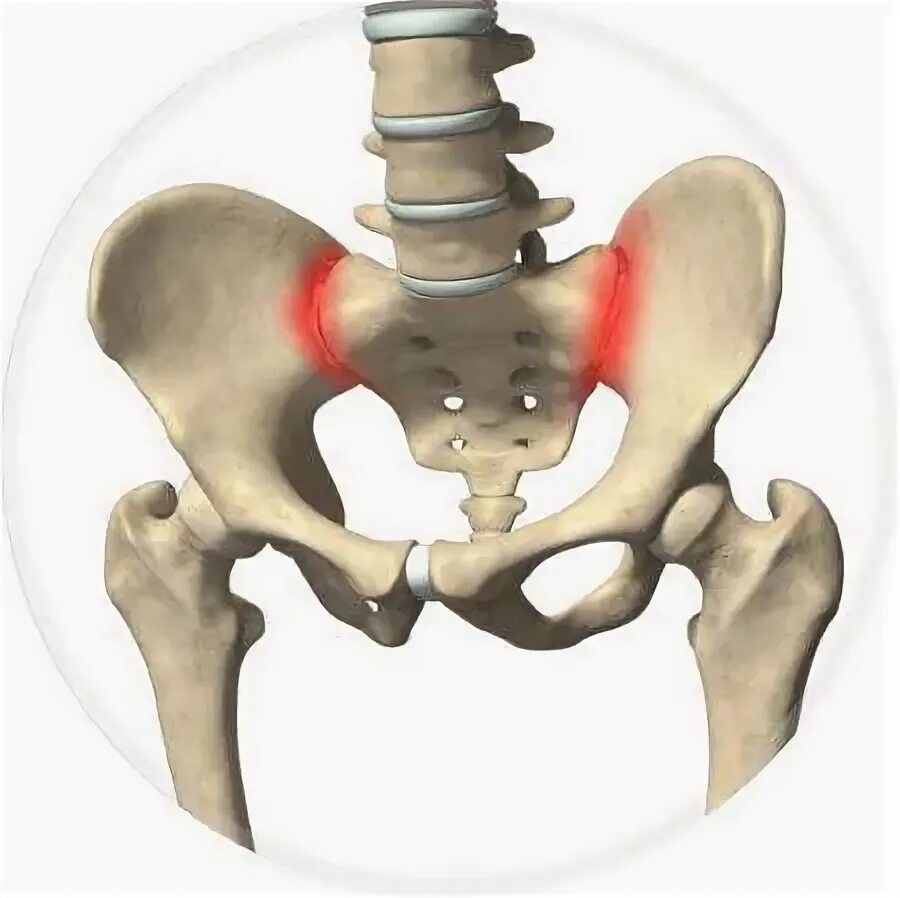

Воспаление подвздошных сочленений